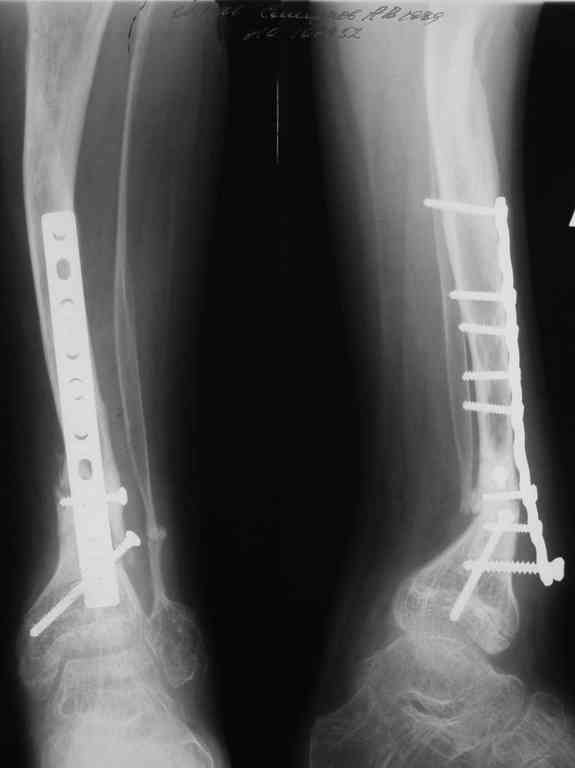

Уважаемые коллеги! В отделении на лечении наблюдается пациент 16 лет с диагнозом: Псевдоартроз костей левой голенив нижней трети. Вальгусная деформация обоих коленных суставов. Укорочение левой н/конечности11см. С 1997 года состоит на учёте у онколога с диагнозом: Рабдомиосаркома мышц тазового дна IV ст., с метастазами в метафизы берцовых костей.Проведена полихимиотерапия, лучевая терапия. В 1998 г. удаление опухоли. Послеоперационный период без особенностей. С 1998 года со стороны онкологии ремиссия, перестройка очагов метастазирования в берцовых костях по типу фиброзной дисплазии.В 1999 г. патологический перелом костей левой голени в н/трети. Лечение в гипсе 1.5 месяца, затем компрессионно-дистракционный остеосинтез апп. Илизарова. Сращения на месте псевдоартроза не достигнуто. С 1999г. ходит без нагрузки на левую н/конечность. Выраженный остеопороз костей н/конечностей. 17.11.05. Операция: Костная пластика зоны псевдоартроза левой б/берцовой кости по типу "русский замок", остеосинтез пластинкой и винтами. После начала нагрузки на конечность рецидив деформации, миграция фиксаторов. 05.12.06. Операция: Удаление фиксаторов из левой голени. Шарнирная остеотомия трети левой б/берцовой кости, остеотомия м/берцовой кости. Дистракционный остеосинтез апп. Илизарова. Устранены основные виды деформации б/берцовой кости. Планировали в дальнейшем несвободную костную аутопластику и интрамедуллярный остеосинтез с блокированием, но кость очень тонкая, склерозированная, выраженный остеопороз. Возникают большие сомнения о возможности сращения даже при этих условиях. Будем рады услышать ваши мнения по дальнейшему лечению данного пациента. Екатериан Анатольевна Озерова, детское отделение УНИИТО

Заранее прошу прощения у неизвестных коллег, но кому пришло в голову синтезировать такую проблемную голень LC DCP по гребню большеберцовой кости? С какой целью выполнена остеотомия? С уважением, Ильин В.С.